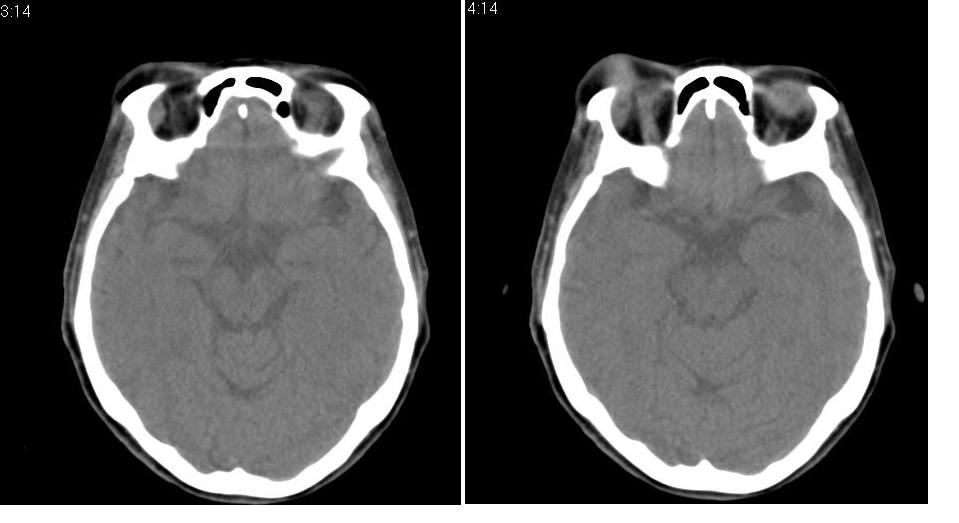

以下是引用zhw974247在2007-5-14 19:34:00的发言:[br]泪腺肿瘤在眶原发性肿瘤中发病率最高,而泪腺混合瘤又是其中最常见者,有良性及恶性二种。良性泪腺混合瘤多见于中年人,病程长,来源于泪腺管或腺泡,也可以起源于副泪腺及先天性胚胎组织残留(泪腺原基)。恶性泪腺混合瘤缺少或无完整的包膜,肿块与眶缘发生粘连,粘连部眶缘有压痛。瘤组织除有良性泪腺混合瘤的结构外,还有癌变的组织构成。瘤组织向眶内浸润,破坏骨质,可发生全身转移,严重者向颅内转移,危及生命。[br]